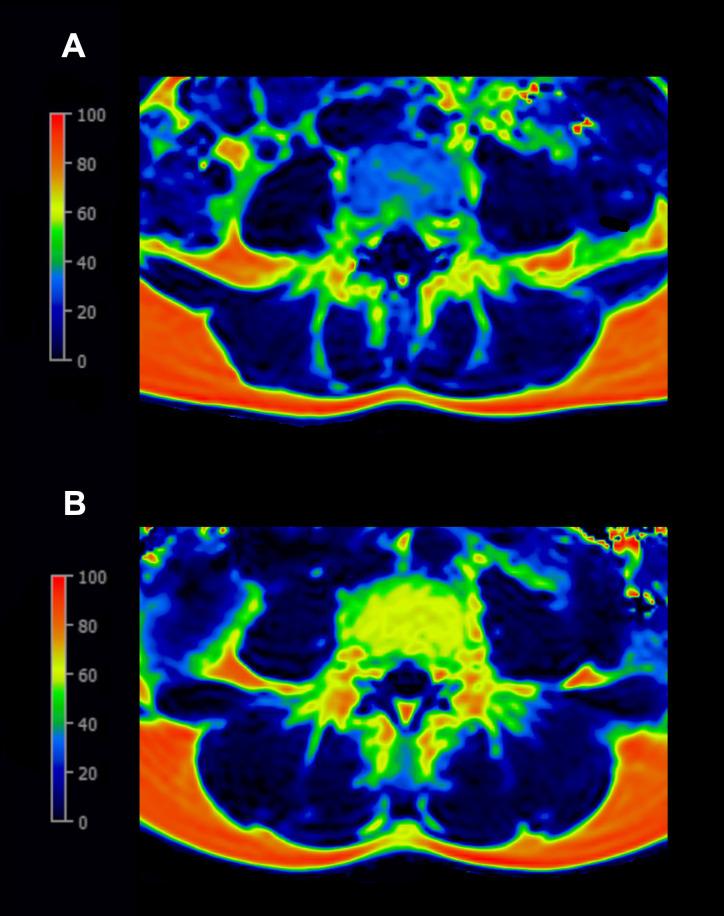

A total of 37 women (mean age 36.3 ± 3.8 years) who were 6 to 15 months postpartum with (n=19) and without (n=18) a history of GDM underwent whole-body 3T MRI, including a chemical shift encoding-based water-fat separation. The PDFF maps were calculated for the vertebral bodies and PSM. The cross-sectional area (CSA) of PSM was obtained. Associations between a history of GDM and PDFF were assessed using multivariable linear and logistic regression models.

The PDFF of the vertebral bodies was significantly higher in women with a history of GDM (GDM group) than in women without (thoracic: median 41.55 (interquartile range 32.21-49.48)% vs. 31.75 (30.03-34.97)%; p=0.02, lumbar: 47.84 (39.19-57.58)% vs. 36.93 (33.36-41.31)%; p=0.02). The results remained significant after adjustment for age and body mass index (BMI) (p=0.01-0.02). The receiver operating characteristic curves showed optimal thoracic and lumbar vertebral PDFF cutoffs at 38.10% and 44.18%, respectively, to differentiate GDM (AUC 0.72 and 0.73, respectively, sensitivity 0.58, specificity 0.89). The PDFF of the AM was significantly higher in the GDM group (12.99 (12.18-15.90)% vs. 10.83 (9.39-14.71)%; p=0.04) without adjustments, while the CSA was similar between the groups (p=0.34).

共有 37 名产后 6-15 个月的妇女(平均年龄 36.3±3.8 岁)参与了本研究,其中 19 名患有 GDM(GDM 组),18 名无 GDM(对照组)。所有参与者均接受了全身 3T MRI 检查,包括基于化学位移编码的水脂分离。计算椎体和 PSM 的 PDFF 图。获取 PSM 的横截面积(CSA)。使用多变量线性和逻辑回归模型评估 GDM 病史与 PDFF 之间的关系。

与无 GDM 病史的妇女相比,患有 GDM 病史的妇女的椎体 PDFF 明显更高(GDM 组:胸椎:中位数 41.55%(四分位距 32.21-49.48%)vs. 31.75%(30.03-34.97%);p=0.02,腰椎:中位数 47.84%(39.19-57.58%)vs. 36.93%(33.36-41.31%);p=0.02)。校正年龄和体重指数(BMI)后,结果仍然具有统计学意义(p=0.01-0.02)。受试者工作特征曲线显示,区分 GDM 的最佳胸椎和腰椎 PDFF 截断值分别为 38.10%和 44.18%(AUC 分别为 0.72 和 0.73,敏感性分别为 0.58,特异性分别为 0.89)。GDM 组的 AM PDFF 明显高于对照组(12.99%(12.18-15.90%)vs. 10.83%(9.39-14.71%);p=0.04),而两组之间的 CSA 相似(p=0.34)。